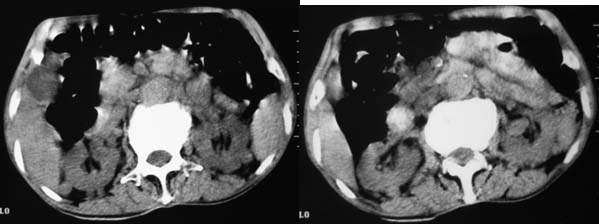

患者男性,74岁,腹部隐痛两月余,血、尿常规检查正常。大腿及腋下皮下各有两枚结节,最大者约3cm,活动度良好,b超提示为囊性。腹部ct平扫见,心包周围、肾周间隙多个大小不一软组织密度结节。

上腹部横断图象显示:心包,胃体小弯侧,肾等器官周围以及肠系膜腹膜后多发的大小不等的小结节样软组织密度影,部分境界不清,未见明显钙化.如此广泛的小结节样影,我认为首先考虑淋巴结肿大.能够引起淋巴结肿大的最常见的原因为:1.炎症(结核常见);2.转移;3.淋巴瘤.其中淋巴结结核不同程度可见钙化,而且这么大范围少见,暂不考虑.

右侧肾上腺区可见软组织密度肿块,密度欠均匀,未见钙化;右肾下极内侧可见实质局限性增厚并呈肿块样突出肾轮廓.